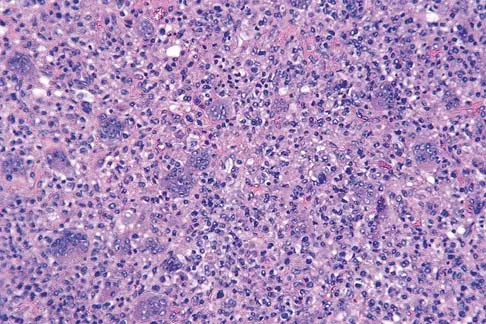

A 14-year-old boy has had knee pain for the past 2 months. He also has a low-grade fever of 101.3 degrees F (38.5 degrees C). Laboratory studies show a WBC count of 12,100/mm3 and an erythrocyte sedimentation rate of 58/h. A biopsy specimen of a lesion in the distal femoral metaphysis is shown in Figure 38. What is the most appropriate treatment?